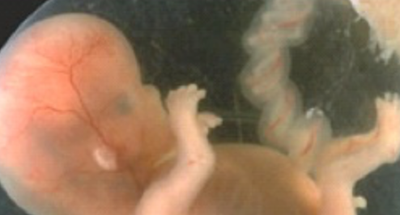

Gravidanza: dalla 9ª alla 12ª settimana